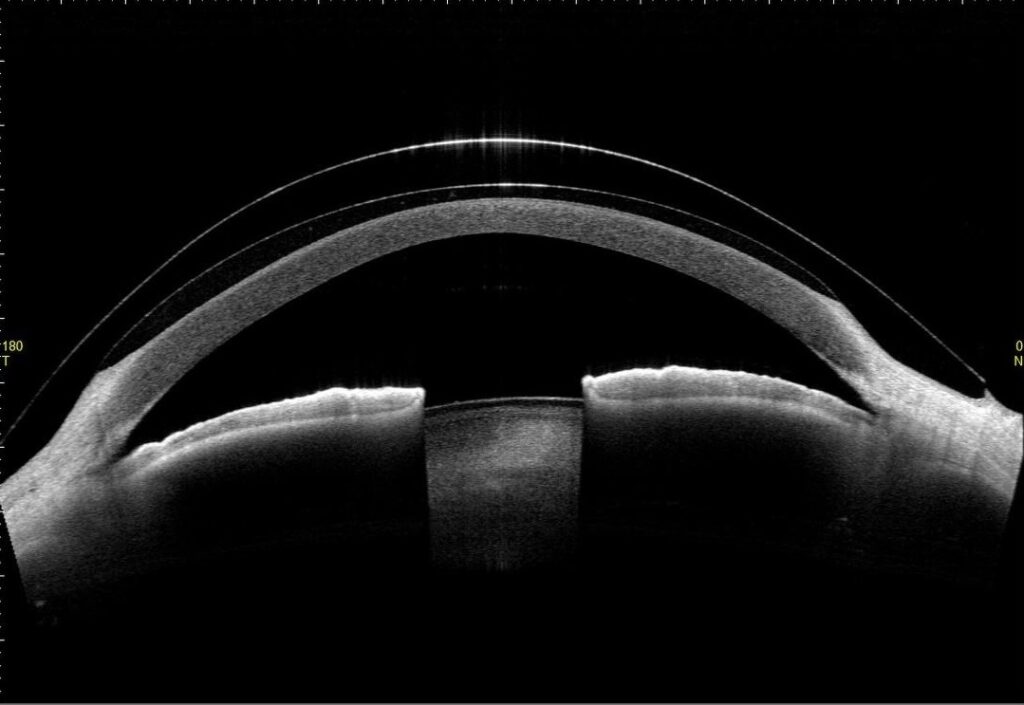

当院では、これまでの眼科的検査では行えなかった、角膜、隅角、虹彩などの断層面の観察や立体構造の数値的解析が行える最新の前眼部三次元画像解析を導入して円錐角膜の早期診断や経過をみることができます。治療は円錐角膜の程度は様々で、突出が軽度であれば眼鏡やソフトコンタクトレンズの装用で良好な視力を得られます。